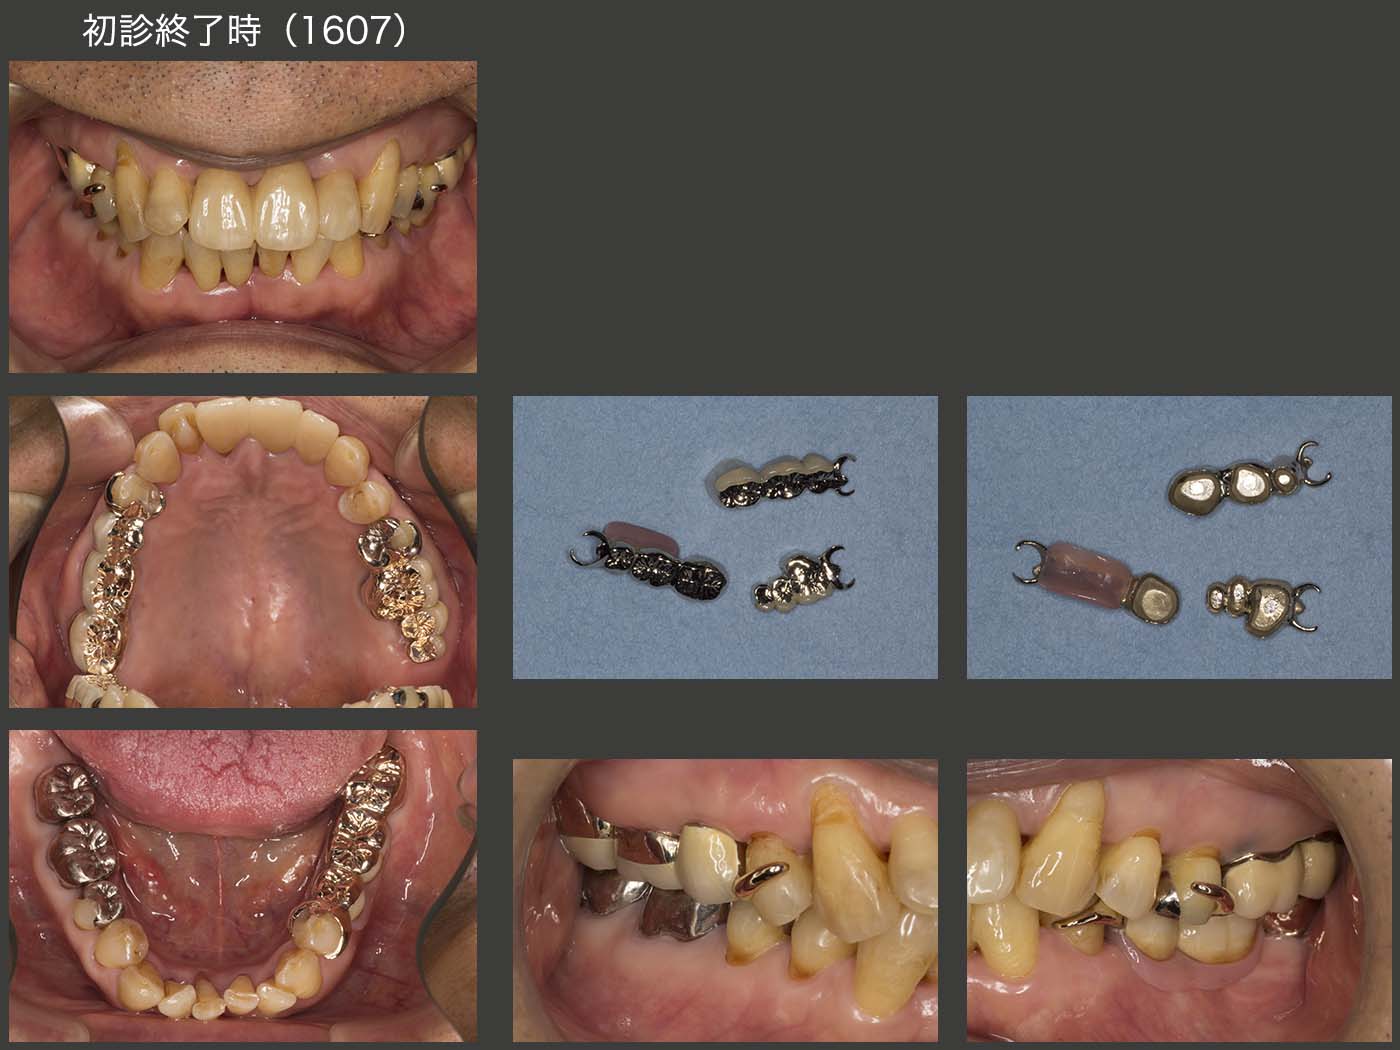

2016年7月,初診終了時の状態.右上7(移植歯)の歯周ポケットは最大5mmの値を示した.左上1は初診時より最大9mmの歯周ポケットがみられたが,歯周基本治療以外,特に治療を施していない.その他の残存歯に問題はみられなかった.なお,初診終了時の残存歯の分布から右側が習慣性咀嚼側になることが予想できる.